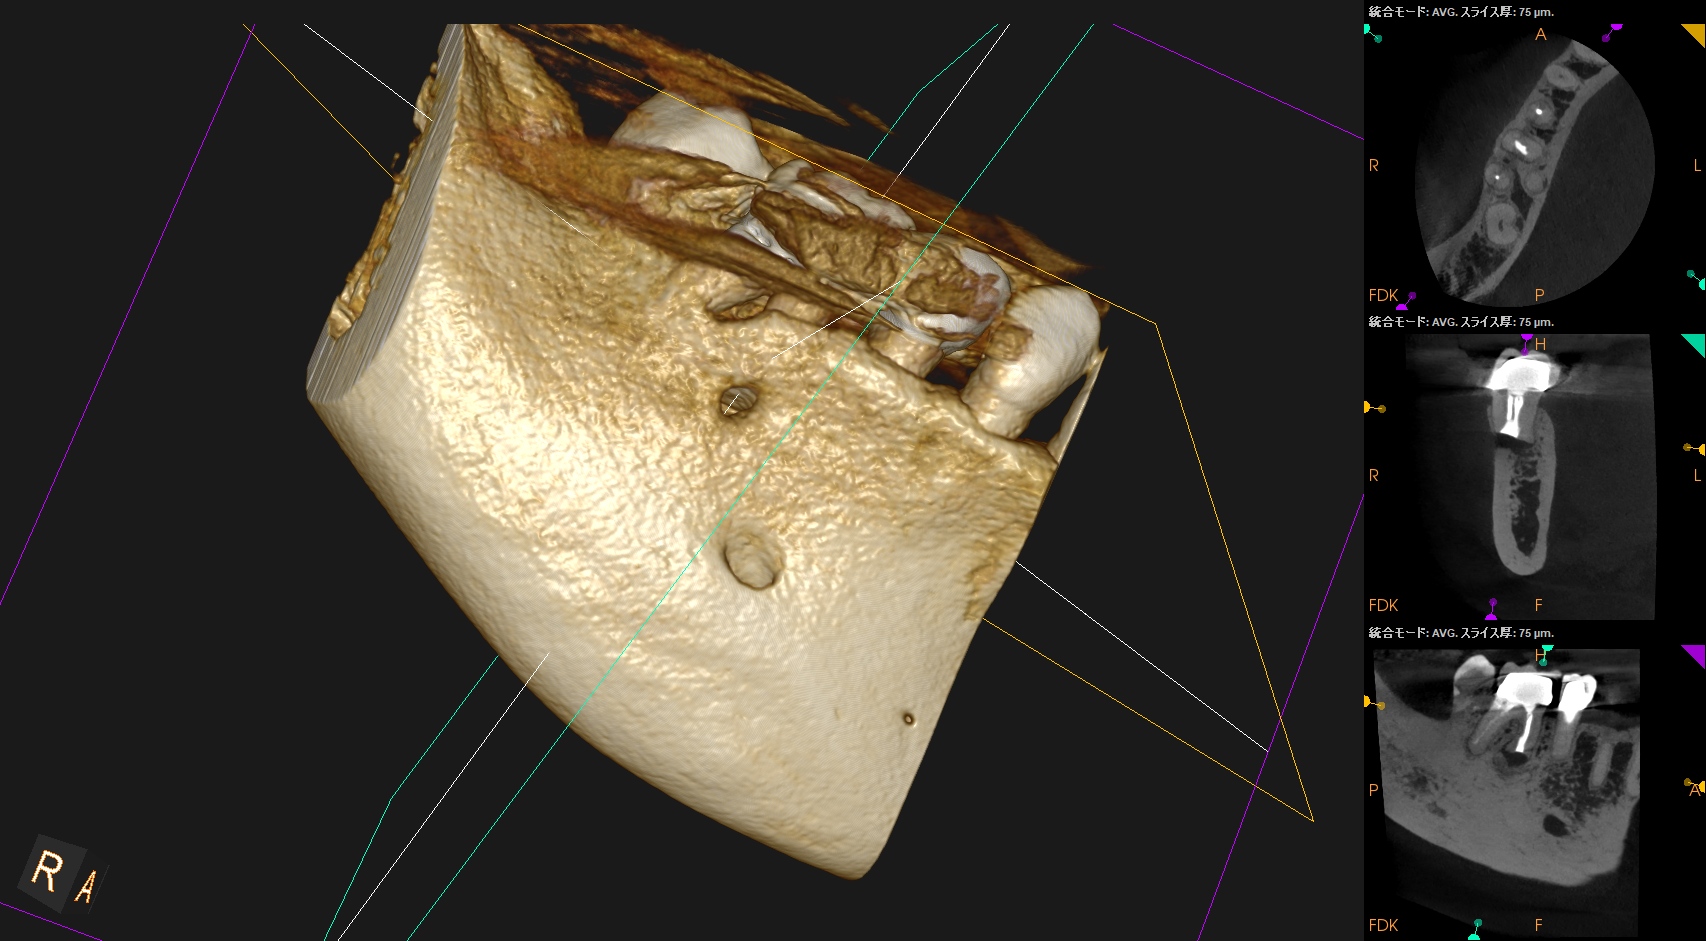

#30 M Apicoectomy 8M recall(2026.2.6)

骨欠損は完治していないが、検査で臨床症状が消失した点と、

術直後が、

骨欠損が今よりも大きく8ヶ月で縮小していることから問題はないと考える。

術直後と比較した。

完治ではないが大幅に問題が解決していることがわかる。